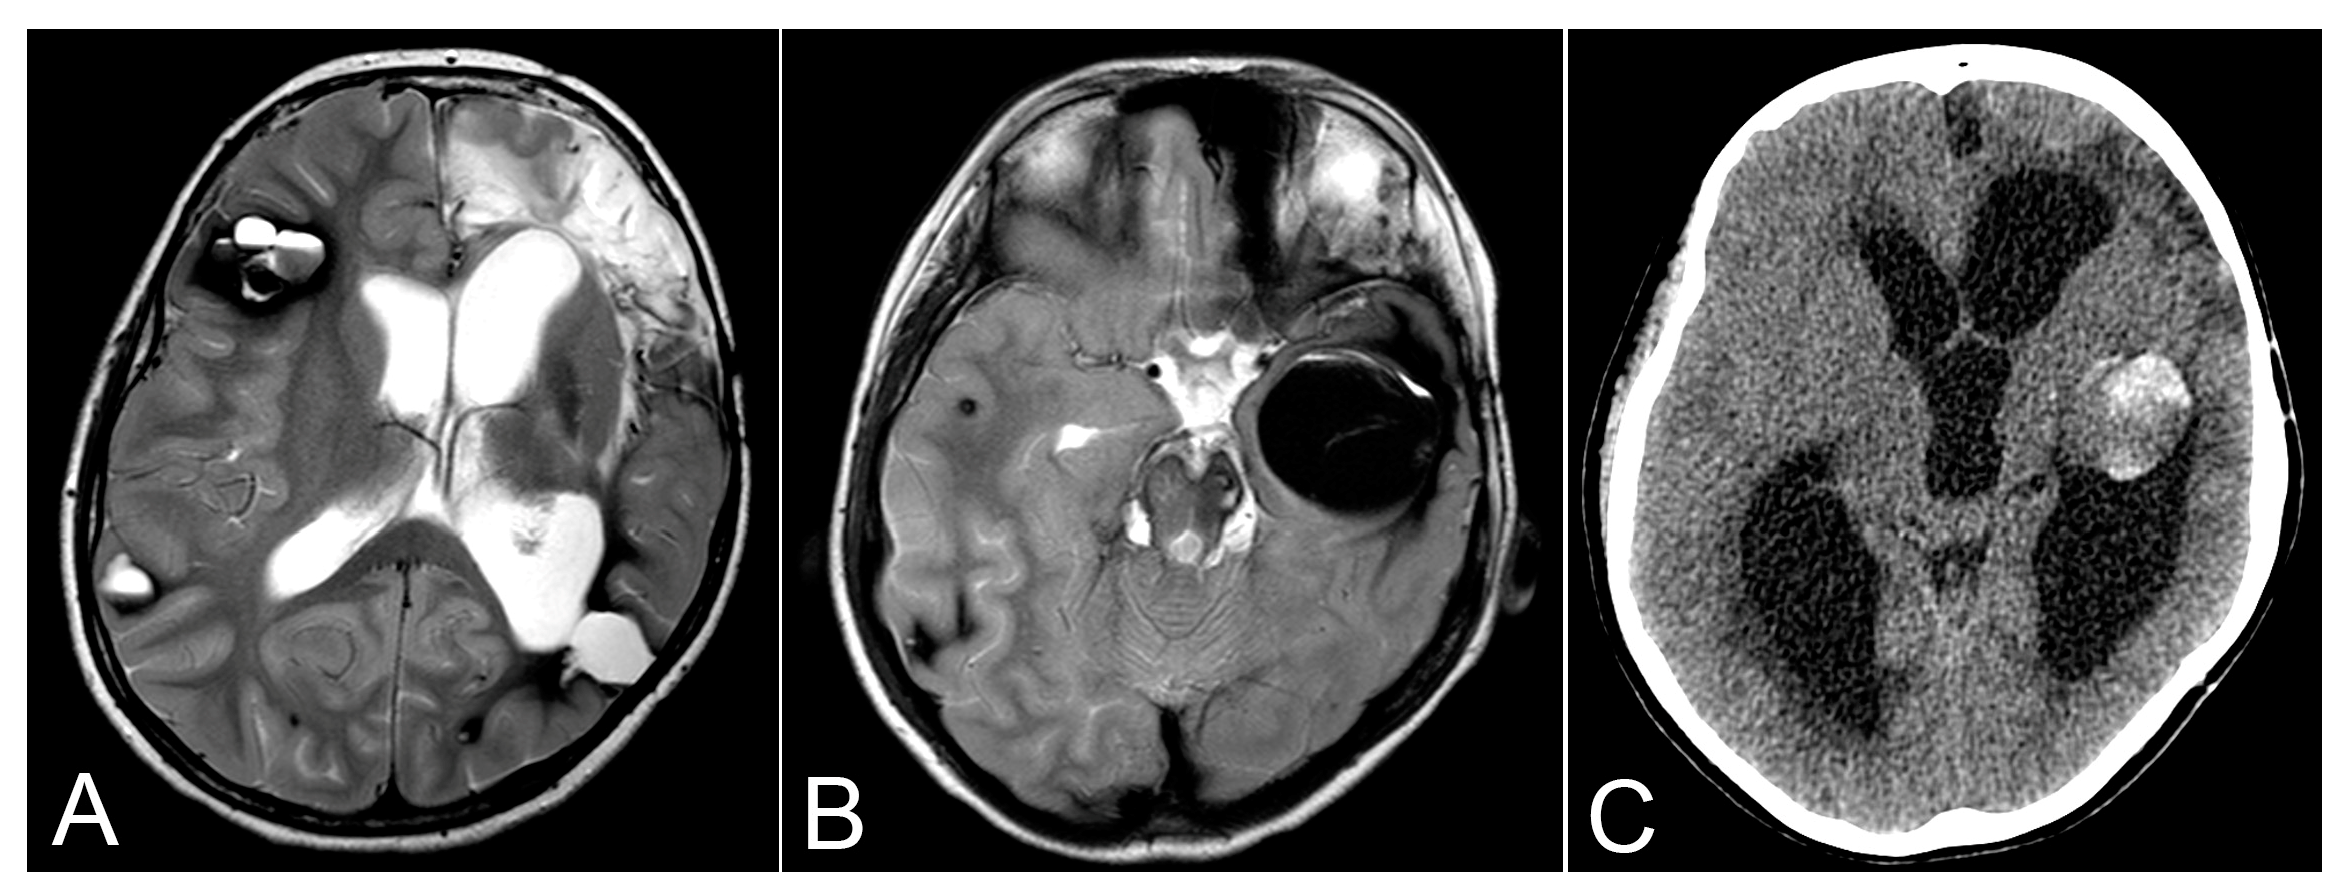

| Follow-up | 5 May 2021 | MRI (Axial T1, Axial T2) | Enlargement of the right frontal CCM, new CCM in the cerebellum with signs of hemorrhage |

| 5th admission | 9 November 2021 | MRI (Axial T2) | Large hematoma in the left temporal lobe, hydrocephalus |

| 5th admission | 2 December 2021 | CT Scan | Progressive enlargement of the ventricular system |